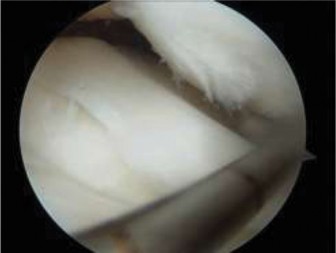

The correct answer is (B). If the patient were asymptomatic, then the discoid meniscus could simply be observed with a return to unrestricted sporting activity. For a younger patient who is intermittently symptomatic and/or elects to not undergo operative intervention, lateral compartment unloader bracing may be appropriate until the patient and/or family agree to intervention. Long-leg casting is not appropriate and will do nothing more than cause stiffness, loss of strength, and range of motion. As the patient is symptomatic, has mechanical symptoms, and has potential tearing seen on MRI, arthroscopic intervention is indicated to examine the meniscus and intervene. The patient is taken to surgery, and intraoperative images ( Figs. 10–31 and 10–32 **) are shown. The next step in management is:**

Figure 10–31

Figure 10–32

Discussion

The correct answer is (C). The arthroscopic images demonstrate a complete discoid meniscus which is covering the entire lateral tibial plateau. As the patient is symptomatic from the meniscus, saucerization is the first step in management. The meniscus is trimmed back using a combination of shavers and biters to a stable peripheral rim, which replicates the width of the native meniscus. Complete meniscectomy would not be indicated in a patient of this age due to the high risk of early onset degenerative arthritis. In fact, even prior to intervention, many discoid menisci have been associated with the development of lateral hemijoint osteochondral lesions. Although chondroplasty may be necessary, the meniscus is the underlying problem causing chondral wear and must be dealt with first. After saucerization is performed, the meniscus is probed and the following arthroscopic image is seen (Fig. 10–33). The next step in management is: